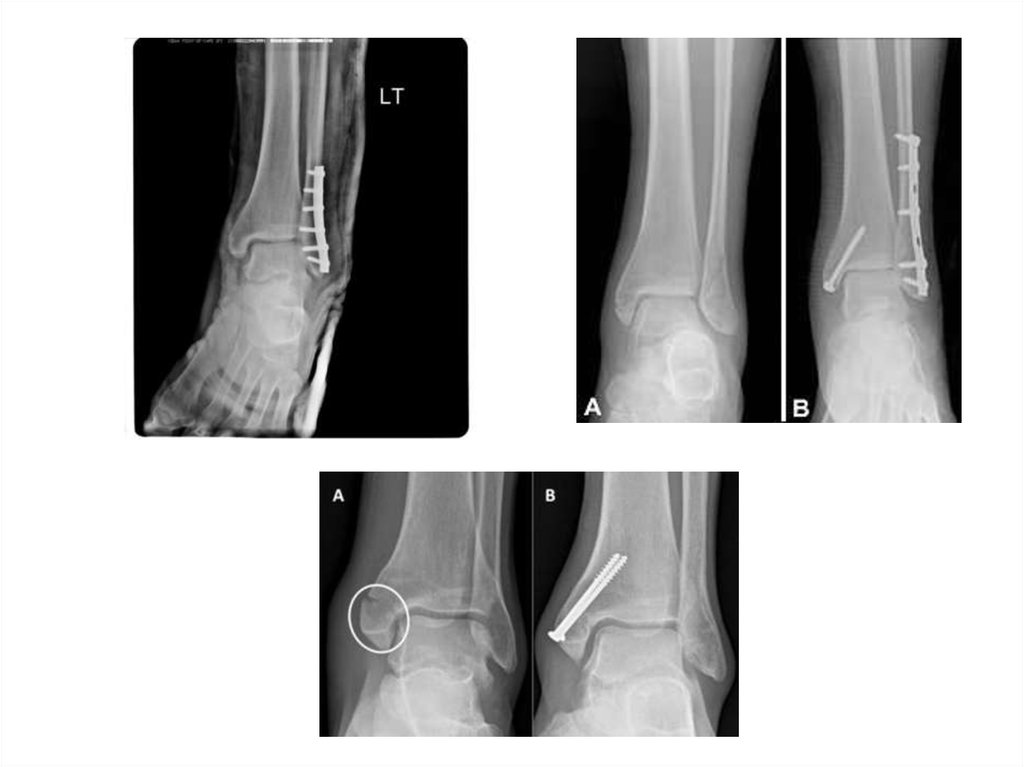

Для остеосинтеза лодыжек применяют маллеолярные и кортикальные

винты, трубчатые или реконструктивные пластины, стержни.

Методы фиксации наружной лодыжки

Способы фиксации

внутренней лодыжки